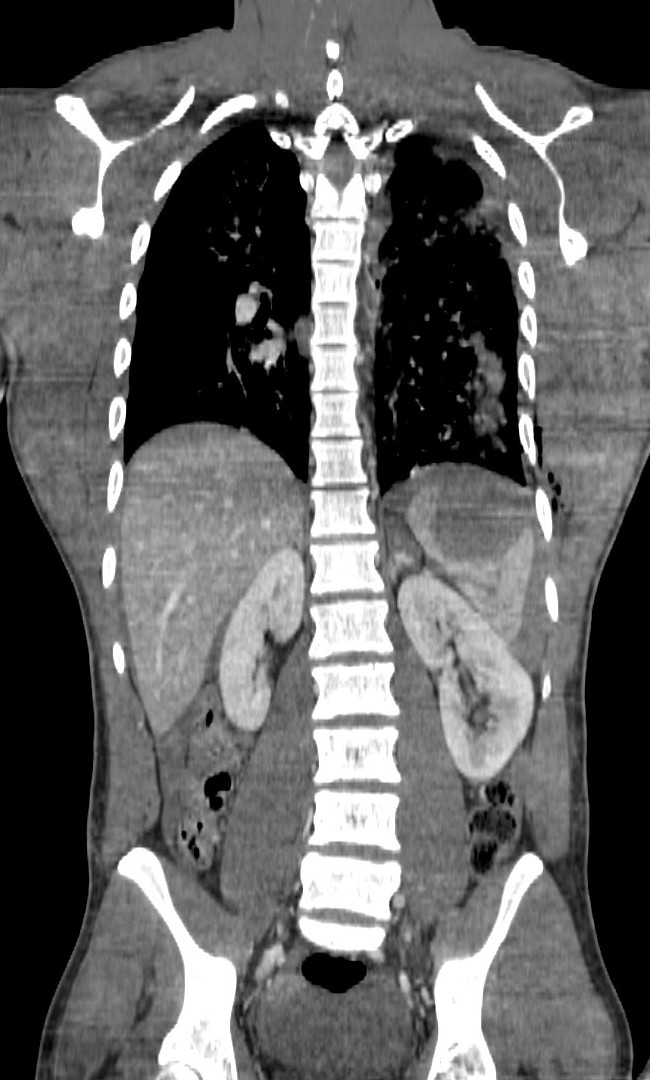

Varón jóven que acude a urgencias tras accidente de moto. Presenta dolor acusado en flanco izquierdo.

Ante estos hallazgos, estamos ante un traumatismo esplénico grado III. Con la edad del paciente y los indicios de inestabilidad hemodinámica, se decidió tratamiento mediante embolización arterial.

Puede asociar lesiones en otras estructuras u órganos intra abdominales:

- Hemidiafragma izquierdo.

- Lóbulo hepático izquierdo.

- Riñón izquierdo.

- Glándula adrenal izquierda.

- Cola pancreática.

TC: Es la técnica de elección, nos permite establecer la graduación de la lesión esplénica así como descartar lesiones en otros orgános, retroperitoneo y pared abdominal. El desarrollo y uso de la TC ha permitido el tratamiento conservador de la lesiones espléncias, así como dotar de mayor información y seguridad a los cirujanos en el caso de ser necesaria una intervención quirúrgica.